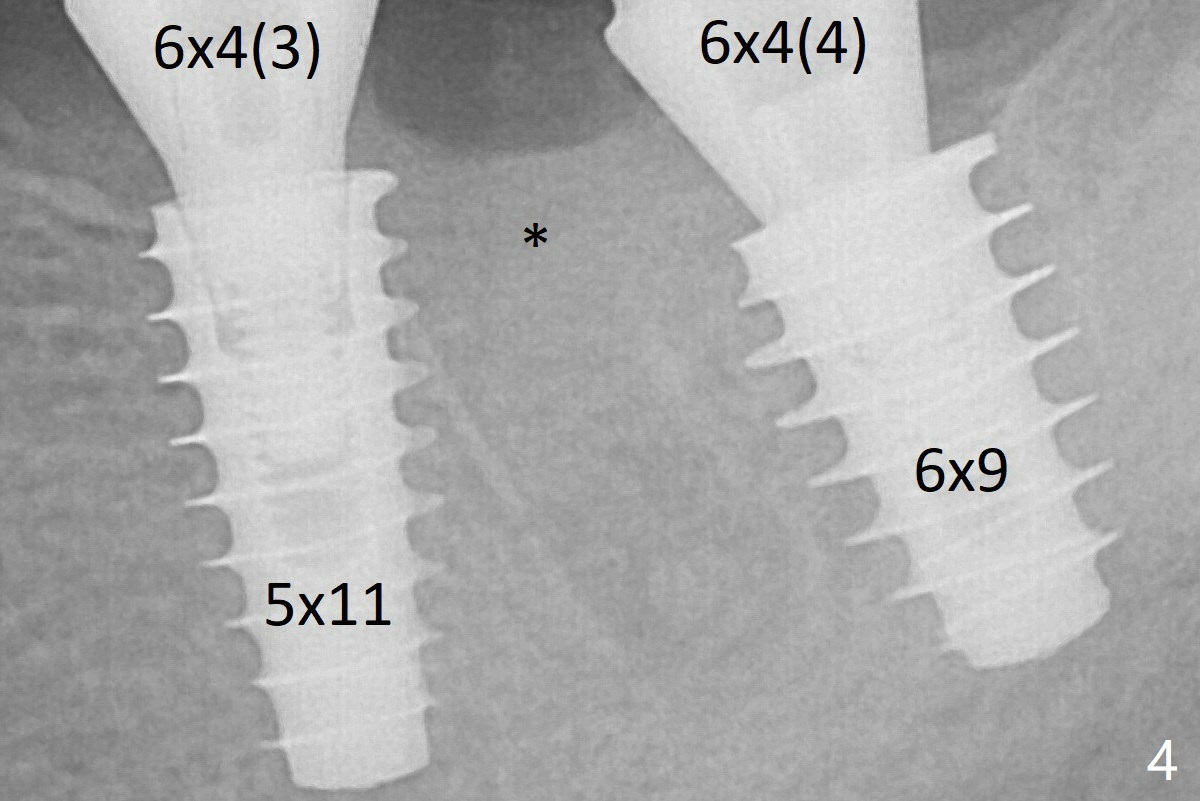

The implant at #19 could be placed more mesially (Fig.4 (*: Vera Graft)).  The implants seem to have osteointegrated 4.5 months postop (Fig.5).